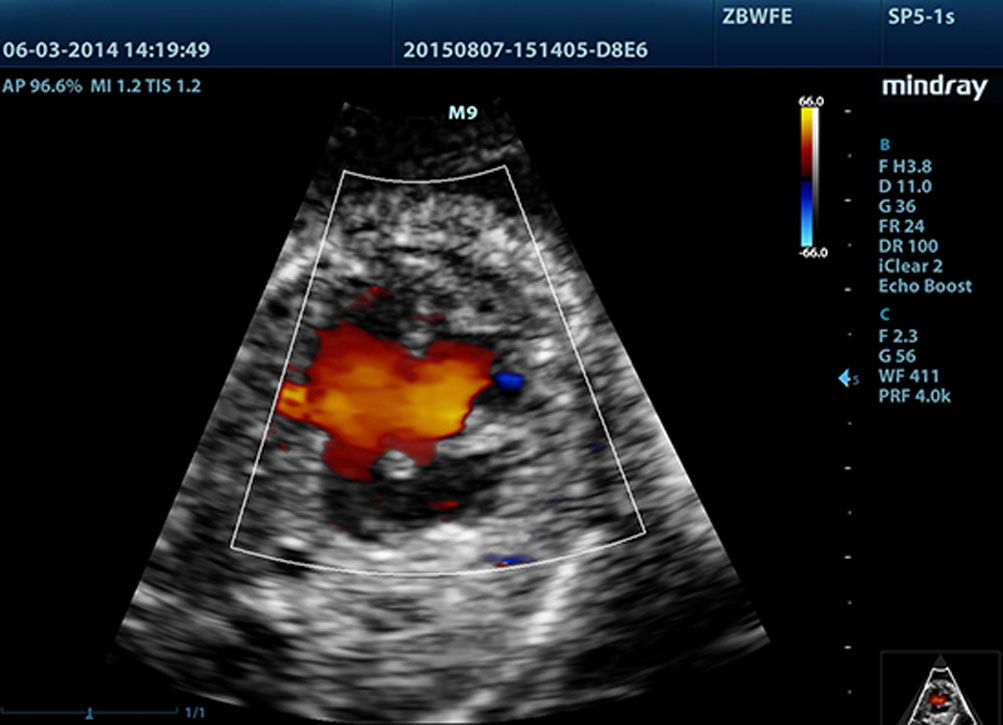

LVO met Stress Echocardiografie

De sterke functionaliteit van de M9 maakt opacificatie van de linker ventrikel onder stress mogelijk, waardoor beter onderscheid kan worden gemaakt tussen hartspierweefsel en bloedvolume, wat een betere weergave geeft van endocardiale oppervlakken. De Stress Echo functie van de M9 biedt een complete oplossing voor echoŌĆÖs onder farmacologische- of inspanningsstress. De oplossing wordt ondersteund door een flexibel rapportagesysteem dat naar persoonlijke behoefte aangepast kan worden.

PSHI? (Phase Shift Harmonic Imaging)

Purified Harmonic Imaging voor een beter contrast en duidelijker beelden met een uitstekende resolutie en minder ruis

Tissue Harmonic Imaging (THI)

THI maakt gebruik van secundaire echoverschillen gegenereerd door weefselgrenslagen. Deze technologie levert aanzienlijk scherper contrast en verbetert de beeldkwaliteit vooral voor technisch moeilijke pati?nten.